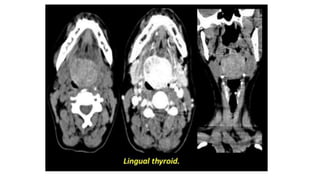

Failure of the thyroid to descend leads to ectopic thyroid tissue.

Ectopic thyroid tissue may occur anywhere along the course of descent

although its commonest at the base of the tongue where it’s called

lingual thyroid. Ectopic thyroid may be associated with hypothyroidism

Failure of thethyroid to descend leads to ectopic thyroid tissue. Ectopic thyroid tissue may occur anywhere along the course of descent although its commonest at the base of the tongue where it’s called lingual thyroid. Ectopic thyroid may be associated with hypothyroidism